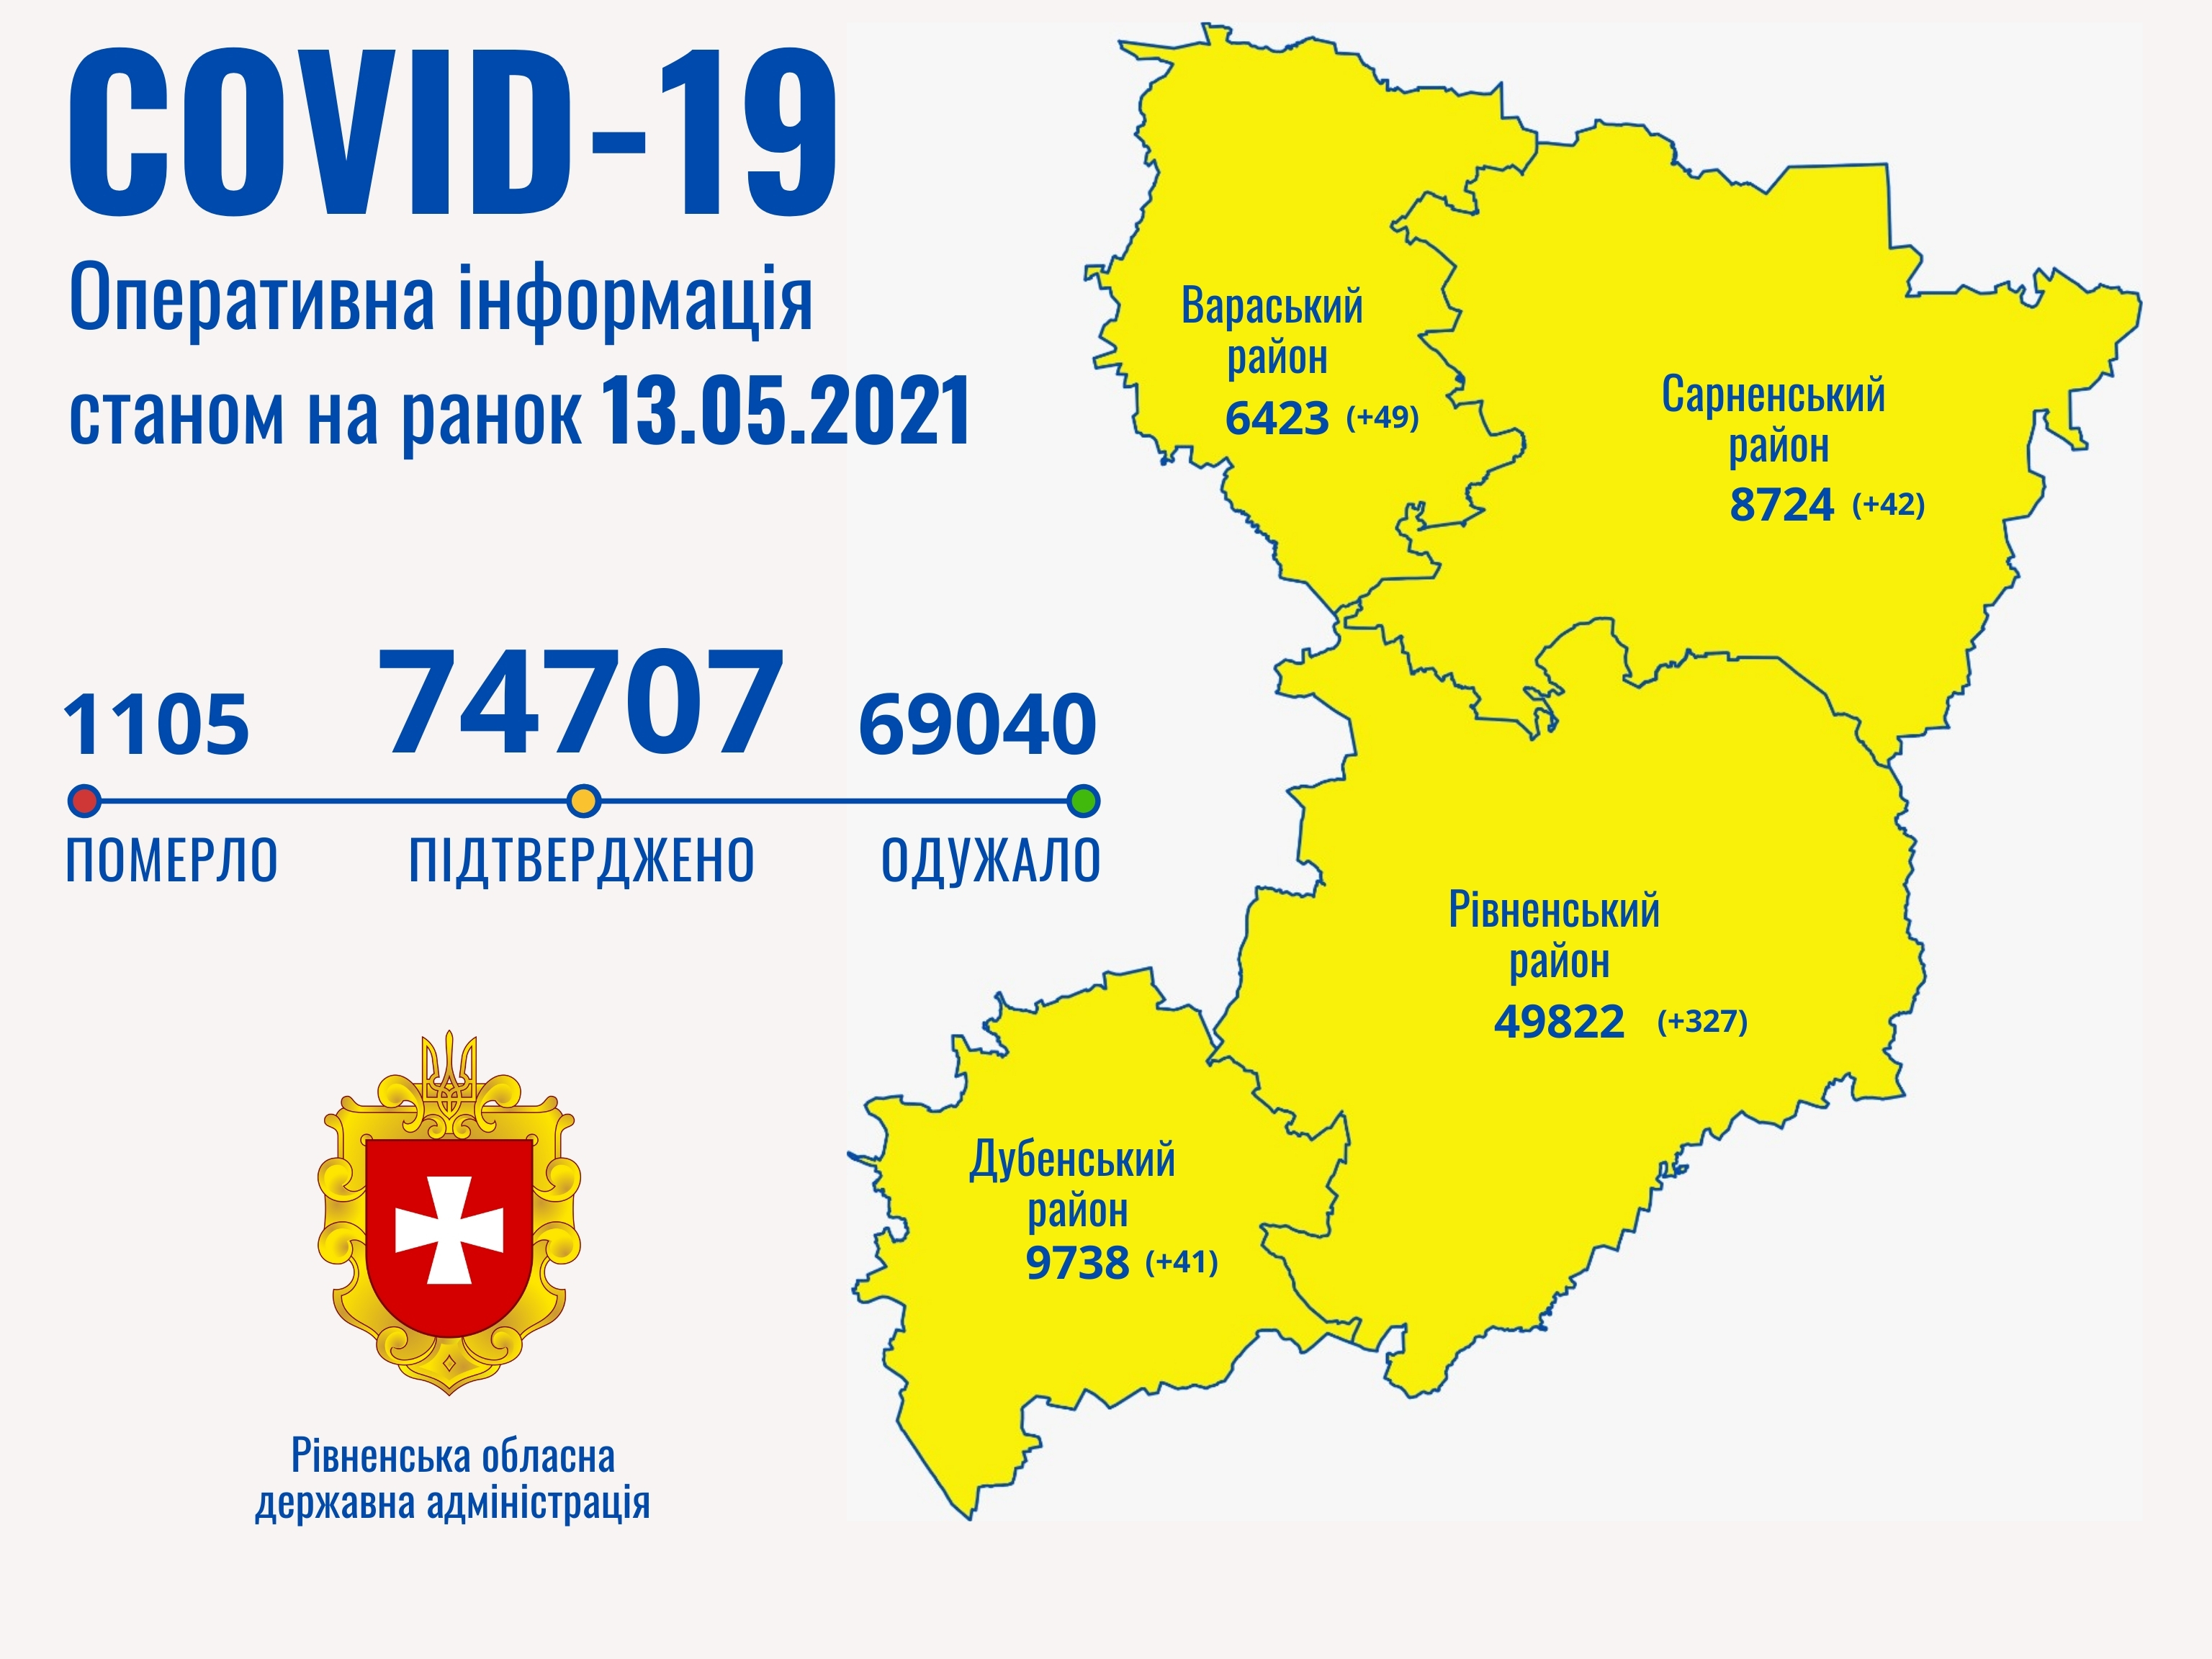

Пів тисячі - у важкому стані, 9 жителів Рівненщини померли за добу від коронавірусу

12.04.2021 10:17